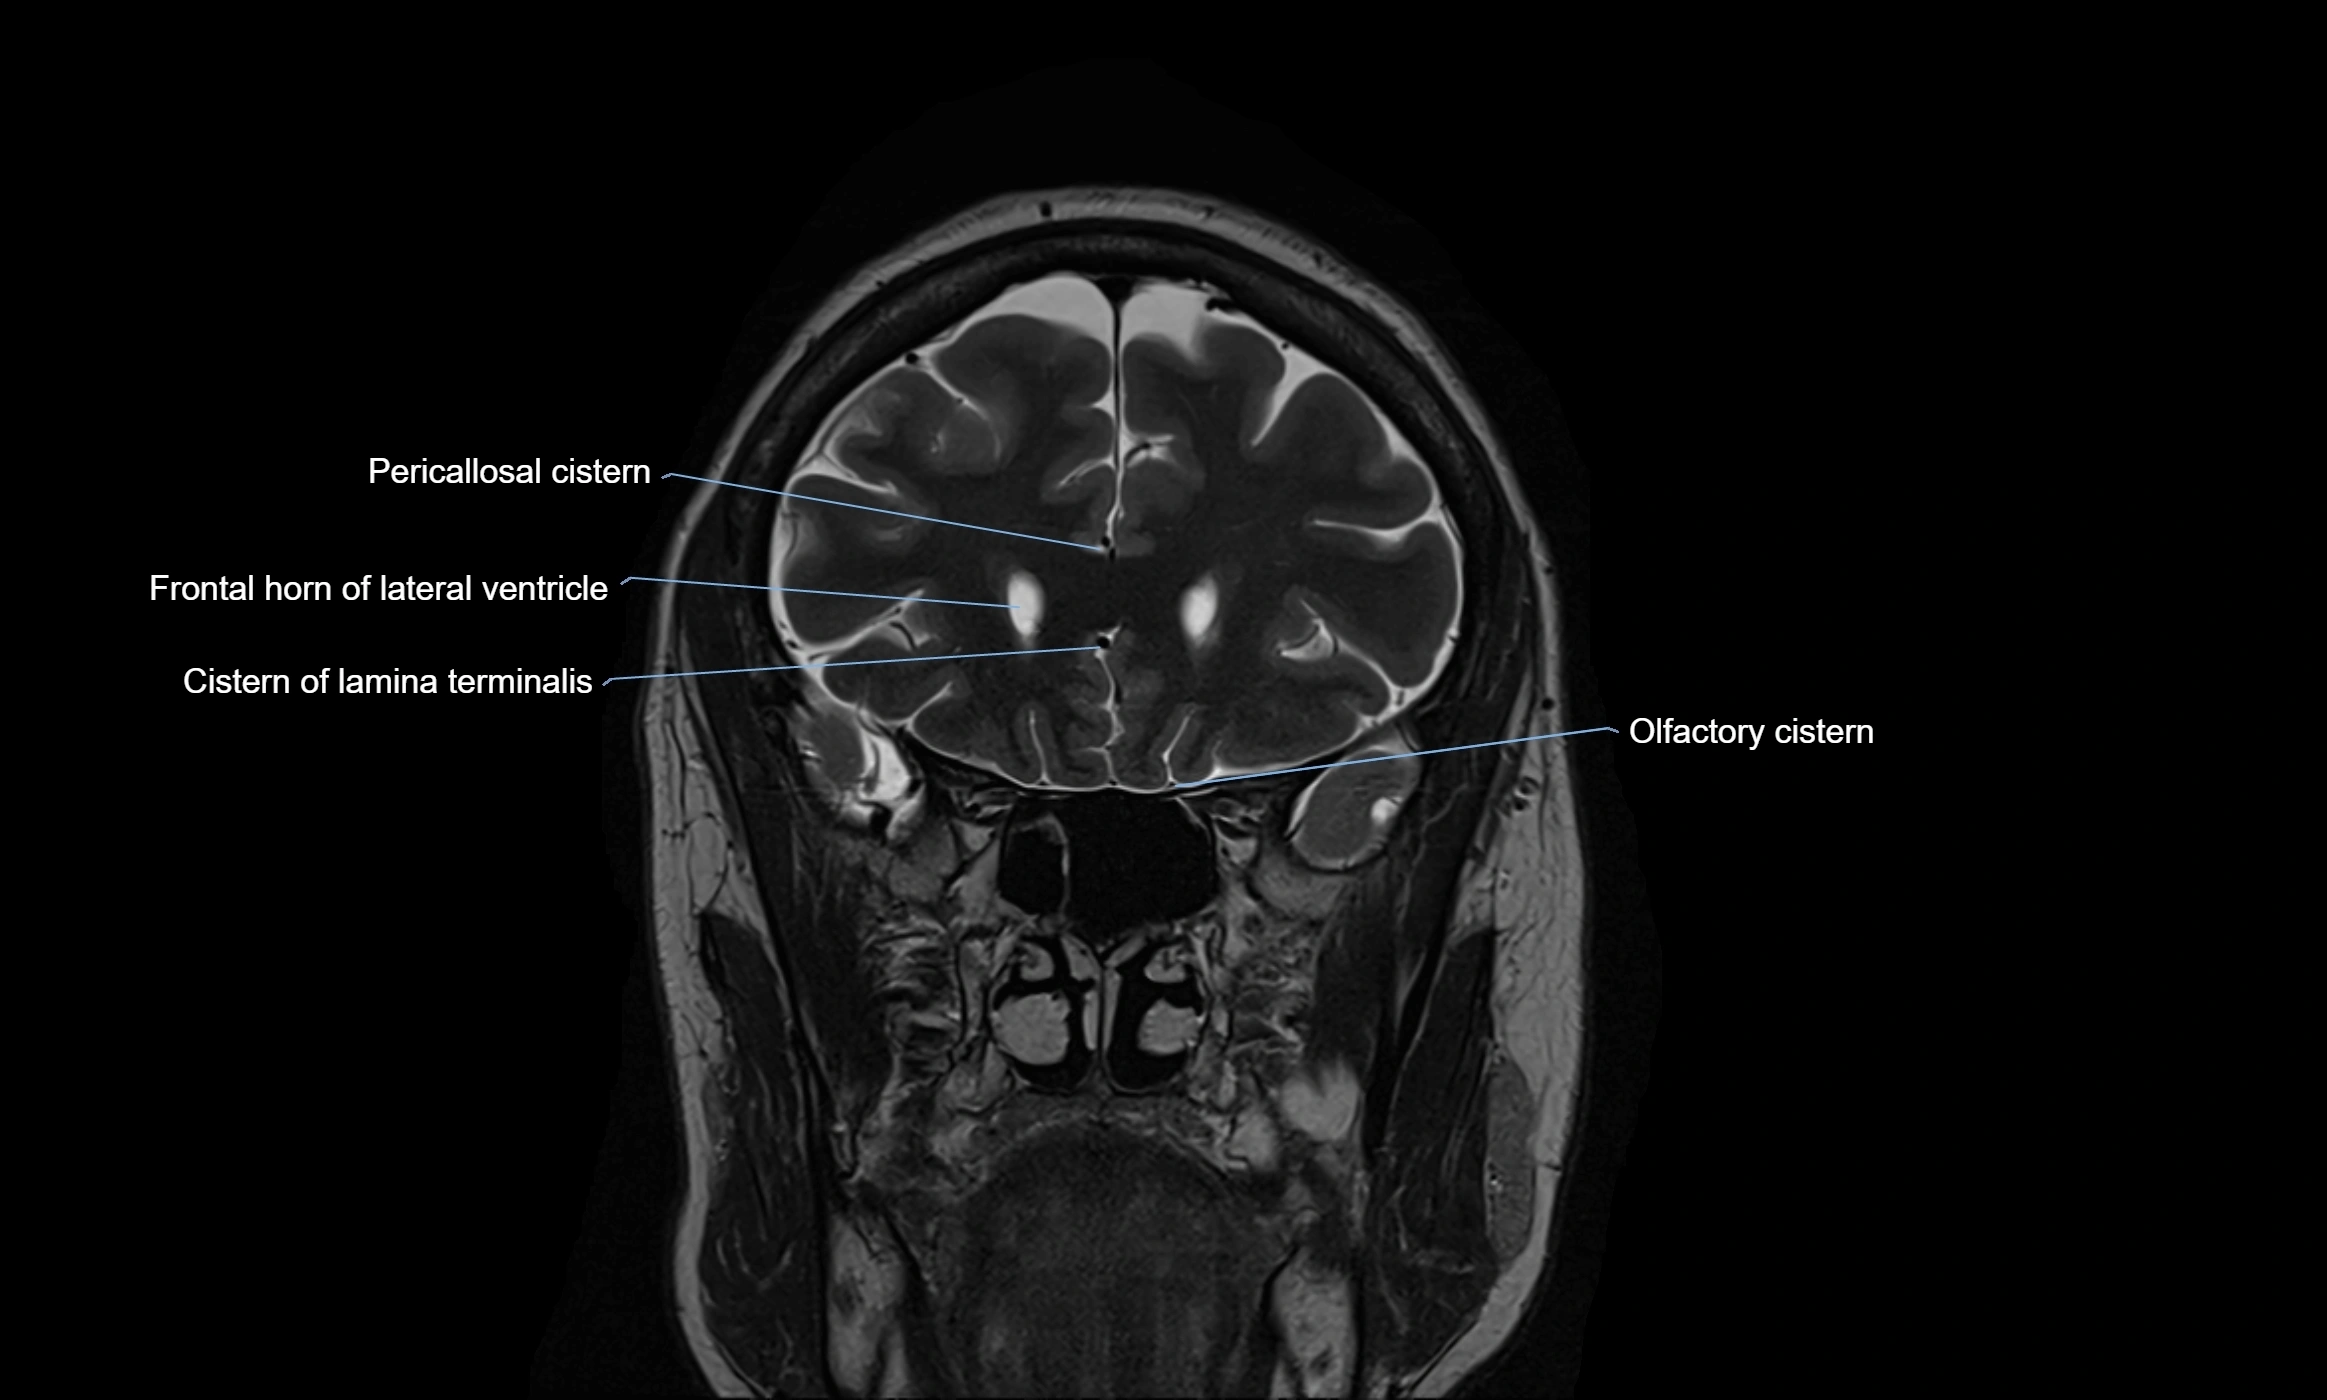

MRI images

image